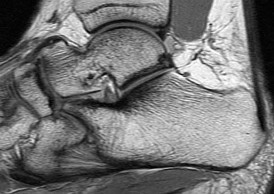

QUESTION 3

Figures 3a through 3h

1

Normal foot

2

Calcaneonavicular (CN) coalition

3

Talocalcaneal (TC) middle facet coalition

4

TC posterior facet coalition

- TC posterior facet coalition

Tarsal coalitions occur when primitive mesenchymal cells fail to differentiate and form the

normal articular separations between the tarsal bones of the hindfoot. Overall incidence is difficult to determine because many affected people are minimally symptomatic or asymptomatic. Symptomatic tarsal coalitions typically present in adolescents as a painful flatfoot; however, there are a number of possible presentations, and occasionally symptoms do not appear until adulthood. Most tarsal coalitions are between the calcaneus and the navicular (CN) and the talus and the calcaneus (TC). Although most TC coalitions are across the middle facet, posterior facet coalitions do occur. Plain radiographic evaluation of suspected tarsal coalition is the mainstay for diagnosis. However, coalitions can be bony or fibrous, and making the diagnosis can be difficult. The addition of CT images to distinguish bony definition and MR images to decipher soft tissue can aid in diagnostics. Bony coalitions appear as definite bony bridging between the bones, while fibrous coalitions are suspected when distortion of the bony anatomy is seen. Bony coalitions are best seen on the oblique view (CN) and Harris axial view (TC). There are a number of secondary signs such as the anteater (AE) sign (elongation of the anterior process of the calcaneus as it extends to the navicular as seen on the lateral view [CN]). talar beaking (traction spur of the talar neck thought to result from abnormal stresses as seen on the lateral view [both CN and TN]), and the “C” sign (a continuous cortical contour from the medial talus to the sustentaculum tali [ST]) as seen on the lateral view (TC). A number of newer signs are not as well known, such as a broad mediolateral dimension of the navicular on the anteroposterior (AP) view (the

navicular is wider than the talar head [CN]), nonvisualization of the middle facet on the lateral view (TC), the brick sign (a normal ST is flat, but a distorted ST is enlarged and curved [CN]), and a tapered lateral navicular bone as seen on the AP view (the medial navicular [CN] is much thicker than the lateral navicular).

Figure 3a shows a flatfoot. Figure 3b shows an MF and TB, but not a C sign. Figure 3c shows a bony irregularity between the calcaneus and the navicular and a WN. Figure 3d shows an MF. Figure 3e shows an MF, but narrowing or loss of the posterior facet. Figures 3f through 3h show medial edema and joint irregularities consistent with a posterior facet coalition.